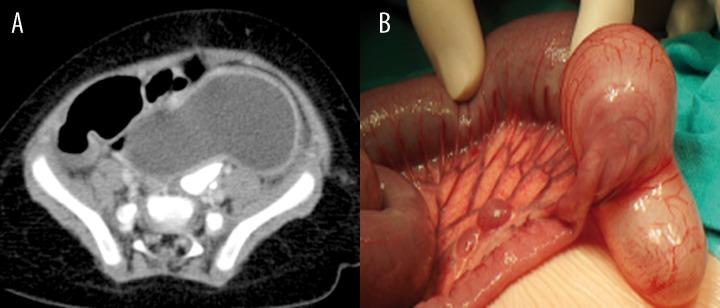

The duplication cysts were identified in the esophagus (n=2), stomach (n=5), duodenum (n=1), terminal ileum (n=5), and rectum (n=1). In four cases, the duplication coexisted with other anomalies, such as patent urachus, Meckel's diverticulum, mesenteric cyst, and accessory pancreas. Clinical manifestation of gastrointestinal duplication cysts was variable, and some of them were detected accidently. Thin- or thick-walled cystic structures adjacent to the wall of neighboring gastrointestinal segment were documented on diagnostic imaging.

Ultrasound and computed tomography are the methods of choice in the evaluation of gastrointestinal duplication cysts. Apart from the diagnosis of the duplication cyst, an important issue is the detection of concomitant developmental pathologies, including pancreatic heterotopy.

重复囊肿见于食管(n = 2)、胃(n = 5)、十二指肠(n = 1)、回肠末端(n = 5)和直肠(n = 1)。4例中,重复畸形与其他异常并存,如脐尿管未闭、梅克尔憩室、肠系膜囊肿和副胰腺。胃肠道重复囊肿的临床表现各异,部分为偶然发现。诊断性影像学检查显示,在相邻胃肠道节段壁旁有薄壁或厚壁囊性结构。

超声和计算机断层扫描是评估胃肠道重复囊肿的首选方法。除了诊断重复囊肿外,一个重要问题是检测伴随的发育性病变,包括胰腺异位。